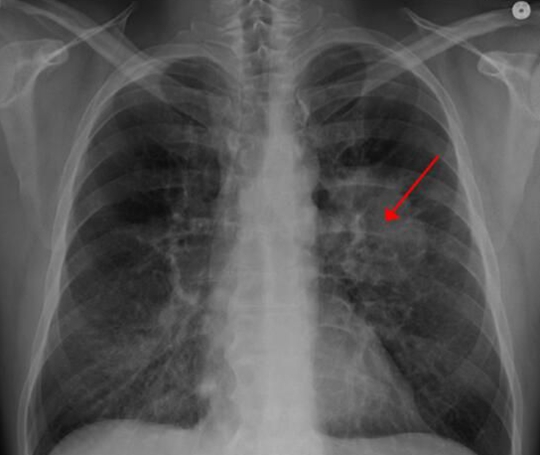

近日,一项刊登在国际杂志Nature Medicine上的研究报告中,来自鲁汶大学等机构的科学家们通过研对数千个健康和癌变的肺部细胞进行研究,初次开发出了肺部肿瘤细胞的全面图谱,研究人员对52种不同的细胞类型进行了区分,研究结果表明,肺部肿瘤或许远比我们认为的要复杂的多,同时研究人员还希望基于本文研究结果来开发出有效治疗多种肺癌的新型治疗方法。

肿瘤是一种非常复杂的细胞生态系统,其能与原始环境相互作用,对肿瘤进行详细研究就需要相应的技能,而知道近些年这些技能才被相继开发出来,研究者能够利用单细胞RNA测序技能来对几乎10万个单一细胞进行研究,他们重点对肿瘤中的癌变细胞和非癌变细胞进行研究,比如血管细胞、免疫细胞和纤维状细胞等,随后研究人员初次绘制出了肺部肿瘤细胞表型的全面图谱。